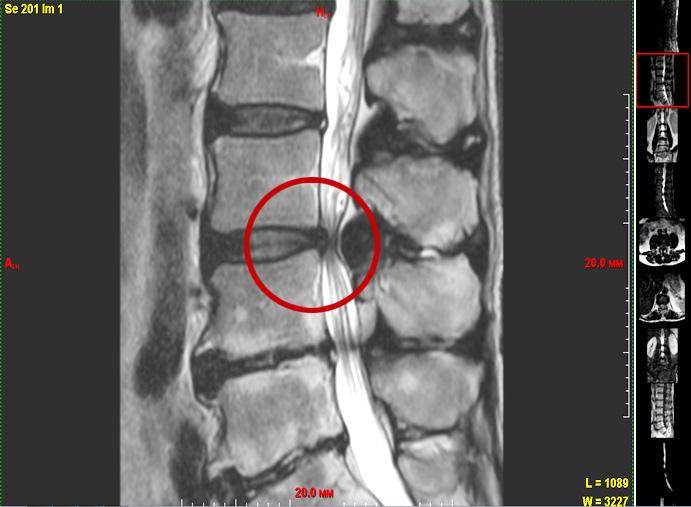

— Оно уменьшается по объему и перестает выполнять роль амортизатора. Нагрузка начинает падать на фиброзное кольцо, которое сзади наиболее тонкое. В этом месте оно быстрее трескается, и в эти трещины начинает выдавливаться пульпозное ядро. Если оно выпячивается немного, до 6 миллиметров, мы говорим о протрузии (выпячивании). Если происходит выпадение грыжи диска — это пролапс.

— Оперируем мы тогда, когда консервативное лечение не приносит результата. Чаще всего, когда или грыжа диска сдавила нервный корешок, или дугоотростчатый сустав значительно увеличился, или есть массивная гипертрофированная желтая связка. Т. е. когда идет компрессия структур спинного мозга или его корешков.